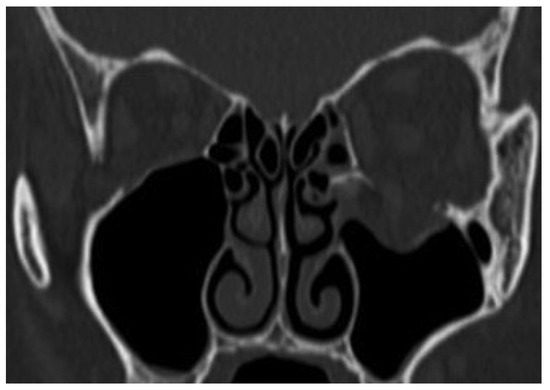

Case 12

A 39-year-old woman sustained facial injuries, and presented with diplopia. She was referred to our clinic by an ophthalmologist for a suspected blowout fracture at 3 weeks after injury. A CT scan revealed bone defect of orbital floor and the displacement of soft tissue into the maxillary (Figure 3). The patient’s left eye movements—up gaze and down gaze—were severely restricted (Figure 4). The diagnosis was a blowout fracture with the orbital floor punched out. Forced duction testing was performed at the beginning of the case to document any preoperative globe restriction. The surgery was performed to reconstruct the orbital floor at 27 days after injury. By transconjunctival approach, the orbital fat and muscle was pulled into the floor cavity, and a 35 mm × 20 mm defect of the orbital floor was seen. A graft was harvested from the sixth right-side rib by splitting it in situ at the size of 50 mm × 15 mm. The split bone was cut and remade into a double leaf using absorbable suture, and gently inserted into the orbital floor without fixation.

Figure 3. Coronal view of CT before surgery. Entrapment of inferior rectus muscle.